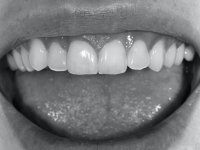

A pre-print was performed to make a crown in dual-cured resin. After a cross-section with a turbine, the infiltrated crown was removed with a microluxador. The dental stump was re-prepared to better define the shape and location of the cervical margin. It was necessary to place composite resin on the buccal surface of the provisional crown to improve its esthetics. The impression was made using a double-mix technique with two-viscosity, quick-setting silicones. In the laboratory, a crown with a ceramic-coated Zr infrastructure was made. After placing it in the mouth, we verified that the crown showed a greater translucency than the symmetrical one, not fulfilling our aesthetic goals. The ceramist had the opportunity to observe the situation in the clinic, collecting records for later rectification. The new crown was placed in the mouth and approved by the patient. The final cementation was done with resin-reinforced glass ionomer cement.